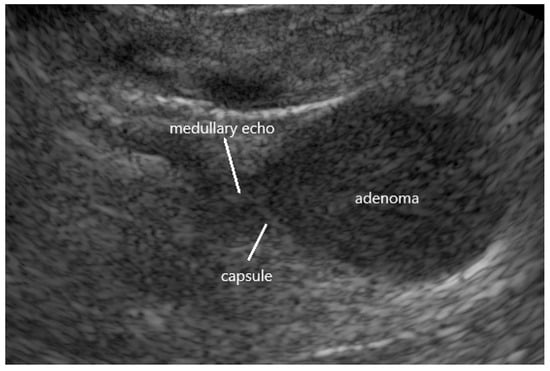

| hypoechoic echogenicity | 82% |

| largely homogenous echostructure | 72% |

| hyperechoic capsular tumor margin | 93% |

| termination of medullary echo at tumor margin | 97% |

| diameter ≤ 2 cm | 77% |

| no/only discrete hyperperfusion (duplex) | 94% |

| tumors fulfilling at least four criteria | 98% |

| tumors fulfilling at least five criteria | 91% |